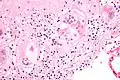

Micrograph of asteroid bodies in pulmonary sarcoidosis. H&E stain.

Asteroid body in sarcoidosis.